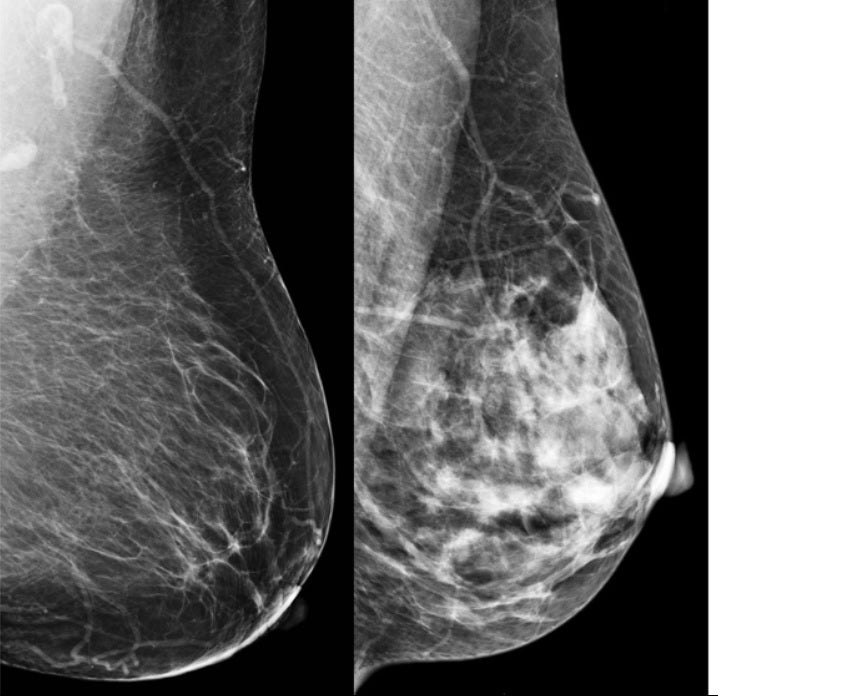

Por otro lado, la ecografía tiene sus propias virtudes. Las mamografías producen una imagen bidimensional donde el tejido glandular de la mama se ve blanco. El problema, es que los tumores ¡también se ven blancos en mamografía! Esta coincidencia entre el tejido glandular normal y los tumores puede ocultar lesiones en mamas muy densas. Así, en mujeres jóvenes o con senos densos, un pequeño cáncer puede «camuflarse» en la mamografía y pasar desapercibido. La ecografía nos ayuda al permitir ver a través de la densidad mamaria y distinguir lesiones ocultas en mamografía. Son un equipo: la mamografía y la ecografía se complementan y no se puede sustituir una por otra. De hecho, estudios muestran que, por cada 1000 mujeres examinadas, la mamografía de cribado detecta aproximadamente 4 a 6 cánceres, y si se añade una ecografía mamaria en mujeres de mama densa, se pueden encontrar 2 o 3 cánceres adicionales. Gracias a esta complementariedad, «no se nos escapa ningún cáncer», tal como señalaba Fuen en el vídeo: cada prueba ve aquello que la otra puede pasar por alto. Ambas técnicas se apoyan mutuamente para lograr la mejor detección del cáncer de mama.

Una mama predominantemente grasa (izquierda) frente a una mama muy densa (derecha). En la mama densa, el tejido glandular aparece blanco igual que un posible tumor, pudiendo ocultarlo y dificultar su detección. En estos casos la ecografía ayuda a ver el tumor que la mamografía podría no diagnosticar.

Entonces, ¿por cuál comenzamos? La manera de empezar por una u otra depende de la edad de la paciente y de otros aspectos como si está embaraza o dando pecho y luego se realizará el estudio complementario con la otra dependiendo de lo que veamos y de la sintomatología. Incluso se podría ampliar el estudio con resonancia magnética en función de los hallazgos de mamo y eco y del tipo de paciente a la que nos encontremos. Tu radiólogo tomará esa decisión de manera acorde a lo que se indica en las guías de práctica clínica.